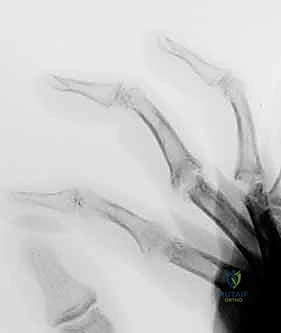

- Inspection: Observe the appearance of the joints and overlying skin. Look for Heberden nodes (DIP OA), mucous cysts (DIP OA), onycholysis or eczema (psoriatic arthritis), and deformities like swan-neck (DIP flexion deformity with secondary PIP hyperextension) or boutonnière (PIP central slip attenuation). Note any erythema, swelling, or skin changes.

- Palpation: Localize tenderness to the affected joint. Assess for warmth or effusions.

This is a critical decision, fellows, a compromise between appearance and function. The ideal posture should replicate the normal digital cascade. We need to achieve a position that allows functional pinch and grasp without creating an unsightly or obstructive deformity.

- DIP Joints and Thumb Interphalangeal Joint: These joints should generally be fused in 0 to 10 degrees of flexion. This allows for optimal tip-to-tip pinch and avoids impingement during grasp.

* PIP Joint:

* Some authors recommend a uniform 40-degree flexion position for all digits.

* Others recommend a cascade: 40 degrees for the index finger, progressing ulnarward in 5-degree increments to 55 degrees in the small finger.

* Clinical Pearl: Many surgeons prefer a slightly more extended position for the index PIP (e.g., 30-35 degrees) to optimize tip-to-tip pinch, which is crucial for this digit.